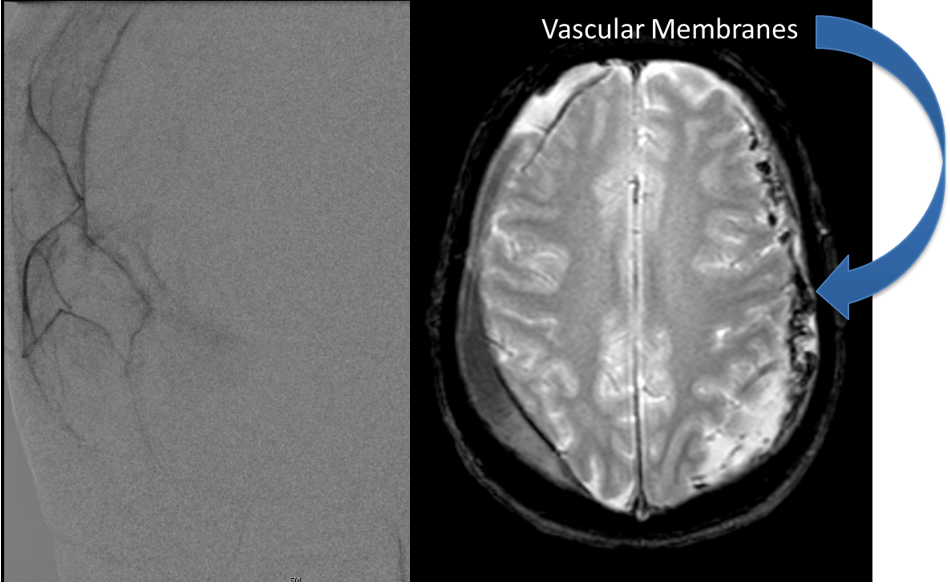

The patient agreed to receive minimally invasive treatment with Bilateral Middle Meningeal Artery Embolization, a new approach to promote resorption of chronic and subacute subdural hematomas in patients that are not improving with conservative measures or have contra-indications to surgical evacuation. Selective catheterization of the Middle Meningeal Artery is followed by transarterial embolization of the territory and inflammatory membranes that are felt to be secreting serosanguinous proteinaceous exceeding the capacity for resorption. MMA embolization was performed bilaterally in this patient. (Figure 2. A and B)

Figure 2. A) Initial right ECA angiogram ; B) Post MMA Embolization; C) Selective Embolization Of Middle Meningeal Artery Membranes using PVA particles (arrows).

Figure 7. Neovascularized membranes within cSDH

Figure 8. Dense contrast staining of vascular membranes during embolization.